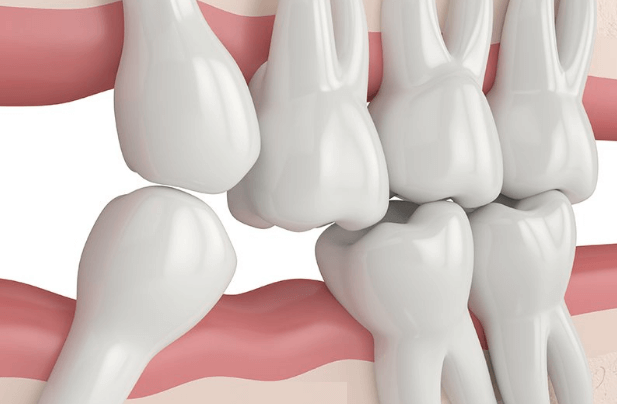

2. 부정교합으로 얼굴 모양 변함

아래 어금니가 없는 경우 위 치아가 아랫니 공간으로 서서히 내려앉고, 윗 어금니가 없는 경우 아래 어금니가 윗니 공간으로 치고 올라가게 됩니다.

부정교합으로 턱 하관의 형태가 변하게 되고 추가적 부정교합 치료 비용과 턱관절의 고통이 뒤따르게 됩니다.